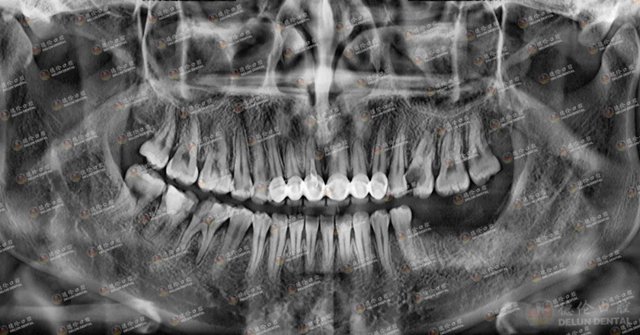

眼见自己的牙齿一天不如一天,2020年5月,刘女士来到德伦口腔区庄旗舰院,寻求崔保亮院长的帮助。经崔院长详细检查,刘女士多颗龋齿龋坏严重,即使做根管治疗也无法保留,只能作拔除处理,后做种植牙。

刘女士术后牙片